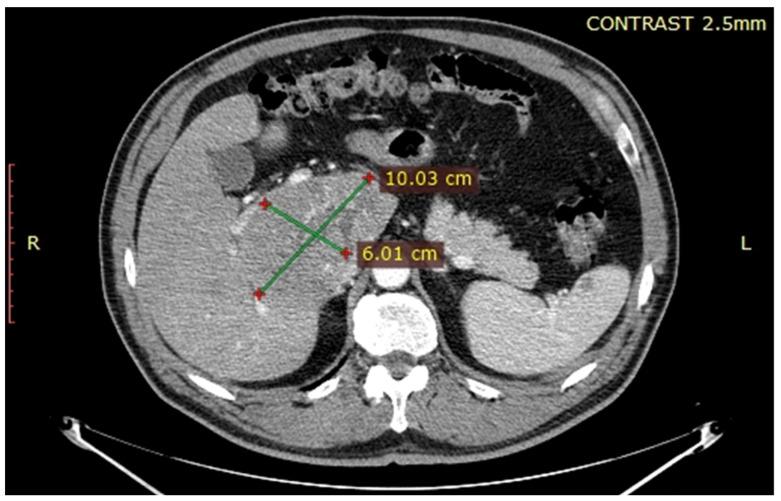

A 61-year-old patient was diagnosed with a caudate lobe tumour invading the inferior cava vein and the right hepatic pedicle.

一名61岁患者被诊断为尾状叶肿瘤侵犯下腔静脉和右肝蒂。